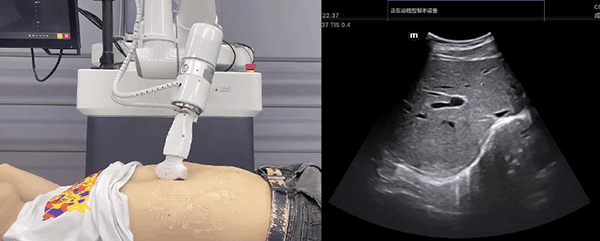

AG庄闲机器人末端搭载超声探头,可以对浅表小器官和外周血管、腹部(肝、胆、胰、肾等器官)进行超声检查。

目前,AG庄闲机器人在生物医药、医疗健康领域的赋能已有显著进展,AG庄闲协作机器人应用场景覆盖了临床试验、试管检测、拭子采集、试管搬运、荧光检测、康复治疗、超声扫查、导诊、消毒、微创治疗、针灸刮痧等。